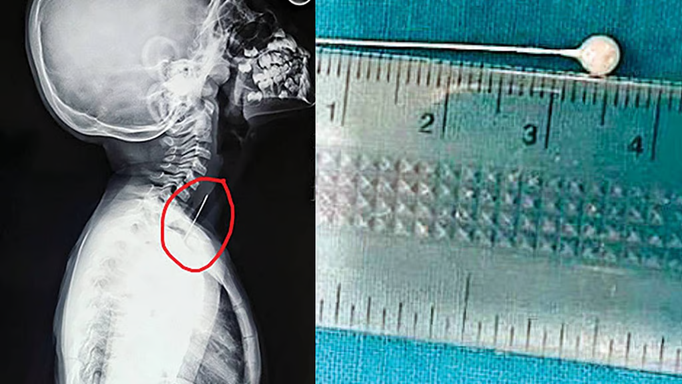

आफिया खुर्शिद को ENT विभाग में ले जाया गया जहां डॉक्टरों ने उसका एक्स-रे निकाला। मात्र वर्षीया बच्ची के गले के एक्स-रे रिपोर्ट में जो कुछ दिखाई दिया, उसे देखकर परिवार की सांसे ही फूल गयी।

आफिया की एक्स-रे रिपोर्ट में उसके गले में श्वास नली के पास धातु का पिन जैसी कोई चीज फंसी हुई दिखाई दे रही थी। श्वास नली में ऐसी किसी धारदार वस्तु के फंस जाने की वजह से दम घुटकर मौत तक हो सकती है। स्थिति की गंभीरता को समझते हुए डॉक्टरों ने देर नहीं की और शाम को करीब 5 बजे उसे सीधा ऑपरेशन थिएटर (OT) में ले गए।

आफिया से बात करके डॉक्टरों को पता चला कि खेलते-खेलते उसने पिन को मुंह में डाल दिया था। विशेषज्ञों का मानना है कि सांस लेते समय हवा के साथ ही पिन श्वास नली से होकर फेंफड़े तक पहुंच गया था। फिर जब सांस छोड़ा गया तो पिन फेंफड़े से बाहर निकल आया। बता दें, श्वास नली में बालों के गुच्छे जैसी बनावट रहती है जो धूल-कणों और जीवाणुओं को रोकने का काम करता है। श्वास नली में पिन के फंसे रहने की वजह से ही आफिया को लगातार खांसी हो रही थी।

मीडिया रिपोर्ट से मिली जानकारी के अनुसार ENT विभाग के एसोसिएट प्रोफेसर दीप्तांशु मुखर्जी के नेतृत्व में जूनियर रेसिडेंट शुभजीत मुखर्जी, सोमदत्ता घन्टी ने यह ऑपरेशन किया। इस बारे में दीप्तांशु मुखर्जी ने कहा कि ब्रॉन्कस्कॉपिक फॉरेन बॉडी रिमूवल पद्धति से पिन को बाहर निकाला गया है।